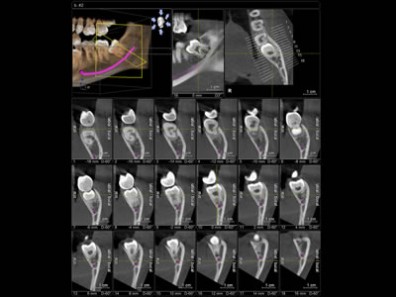

Tomografia Computadorizada Cone Beam

Localização de dentes inclusos e/ou supranumerários e os 3° molares ( relação com o canal mandibular)

Fraturas, reabsorções e perfurações radiculares